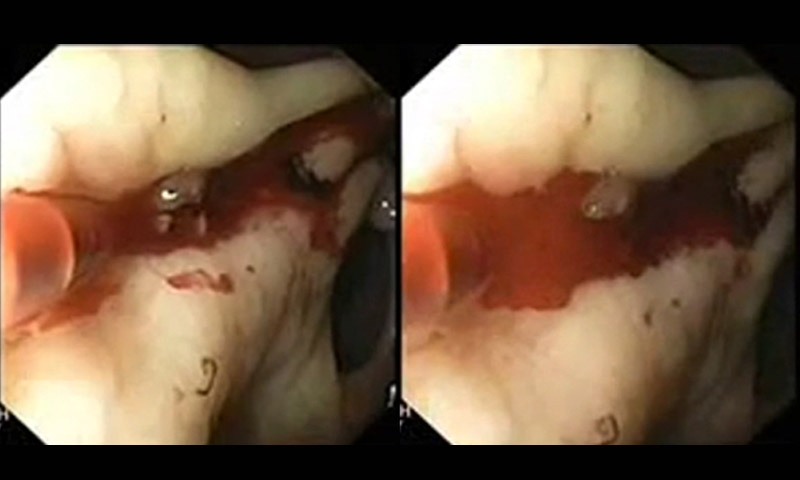

- การส่องกล้องทางเดินอาหาร กรณีเลือดออกทางเดินอาหารส่วนบน จะส่องกล้องผ่านเข้าไปทางปาก สามารถตรวจสอบได้ตั้งแต่หลอดอาหาร กระเพาะอาหาร และลำไส้เล็กส่วนต้น หากมีเลือดออกทางเดินอาหารส่วนล่าง จะส่องกล้องเข้าไปทางทวารหนัก ตรวจสอบลำไส้ใหญ่ เพื่อดูว่ามีรอยโรคที่ทำให้เลือดออกหรือไม่ ตรงจุดใด สามารถรักษาได้ทันทีหรือไม่

หากพบว่ารอยโรคมีแนวโน้มว่าจะทำให้เลือดออกอีก สามารถให้การรักษาได้ทันที ผ่านการส่องกล้อง ซึ่งมีหลายวิธีขึ้นอยู่กับรอยโรคที่เป็น ถ้าเป็นแผลและมีลักษณะเป็นเส้นเลือด อาจเริ่มตั้งแต่ฉีดยา ใช้ความร้อนจี้ หรือใช้คลิปหนีบบริเวณที่อาจมีเลือดออกได้ อย่างไรก็ตาม โอกาสส่องกล้องไม่สำเร็จมีได้บ้าง แต่น้อยกว่าร้อยละ 10 ซึ่งก็มีทางเลือกอื่นคือใช้วิธีเอกซเรย์ดูตำแหน่ง เพื่อเข้าไปทำการอุดรอยที่ทำให้เลือดออก ส่วนการผ่าตัดแพทย์จะพิจารณาเป็นทางเลือกสุดท้าย กรณีที่ให้การรักษาด้วยวิธีอื่นแล้วไม่ได้ผล และโรคเป็นรุนแรงมาก